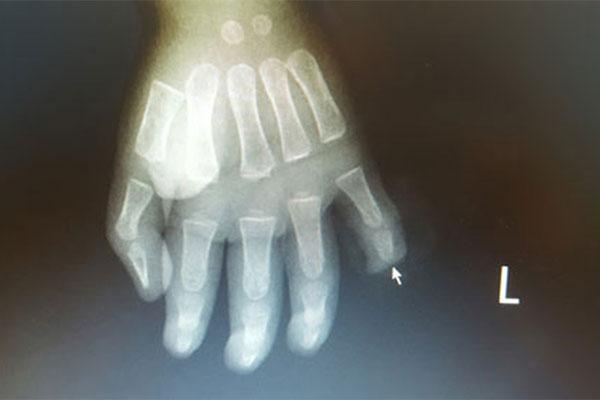

Bệnh nhi nhập viện với vết thương đứt rời đốt 3 ngón 5 bàn tay trái, chảy rất nhiều máu. Các bác sĩ đã tiến hành phẫu thuật tạo mỏm cụt ngón và đốt bàn ngón tay số 5 cho bệnh nhi.